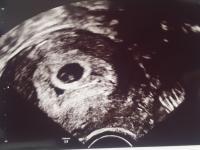

Der Herzschlag des Babys kann in der Regel zwischen der 6. und 8. Schwangerschaftswoche auf dem Ultraschallgerät erkennbar sein. Bei einem Frauenarzttermin in der 6. Schwangerschaftswoche besteht eine gute Chance, den Herzschlag zu sehen. Allerdings hängt dies von verschiedenen Faktoren ab, wie zum Beispiel der Position des Embryos in der Gebärmutter und der Qualität des Ultraschallgeräts.

Bei einer Ultraschalluntersuchung in dieser Zeit wird Ihr Frauenarzt wahrscheinlich die Fruchthöhle und den Dottersack sehen können. Der Dottersack spielt eine wichtige Rolle bei der Blutbildung und übernimmt vorübergehend wichtige Stoffwechselfunktionen.

Bestimmt fragt ihr euch, ab welchem Zeitpunkt ihr das Herz auf dem Ultraschallgerät schlagen sehen könnt. In der Regel könnt ihr den Herzschlag eures Kindes zwischen der 6. und der 8. Schwangerschaftswoche auf dem Ultraschallgerät erkennen.

Zwar kann der Herzschlag des Embryos bereits gegen Ende der 6. Schwangerschaftswoche zu erkennen sein, doch auch wenn euer Frauenarzt das Herz auf dem Ultraschall noch nicht pochen sieht, braucht ihr euch keine Sorgen zu machen. Spätestens in der 8. Schwangerschaftswoche ist der Herzschlag erkennbar. Ob der Herzschlag bereits in der 6. Schwangerschaftswoche zu erkennen ist, hängt unter anderem davon ab, welche Position der Embryo in eurer Gebärmutter eingenommen hat und natürlich auch von der Qualität des Ultraschallgeräts sowie der Entwicklung des Embryos.

Was der Frauenarzt jedoch mit großer Gewissheit sehen wird, ist die Fruchthöhle, welche sich in der Gebärmutter gebildet hat, und den Dottersack. Der Dottersack ist verantwortlich für die Blutbildung und übernimmt vorerst die wichtigen Stoffwechselfunktionen.